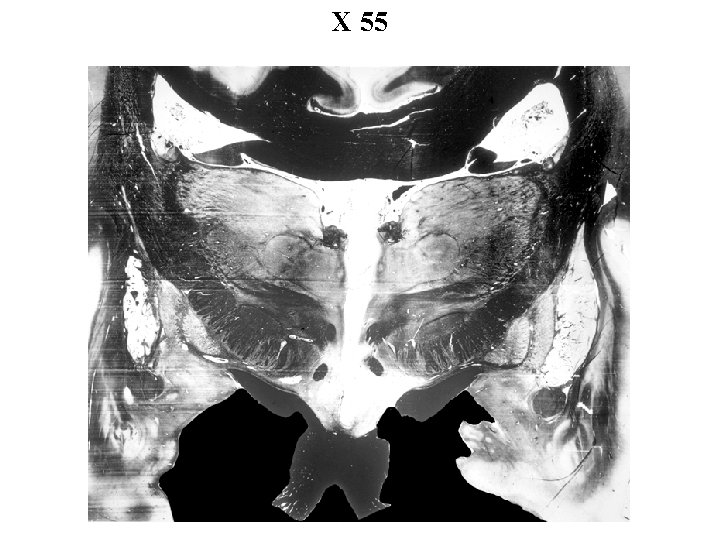

X 55